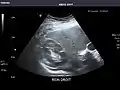

Kidneys: Right and left kidneys measure 11.5 cm and 12 cm in length respectively. No hydronephrosis. Small left lower pole kidney cyst.

Left kidney